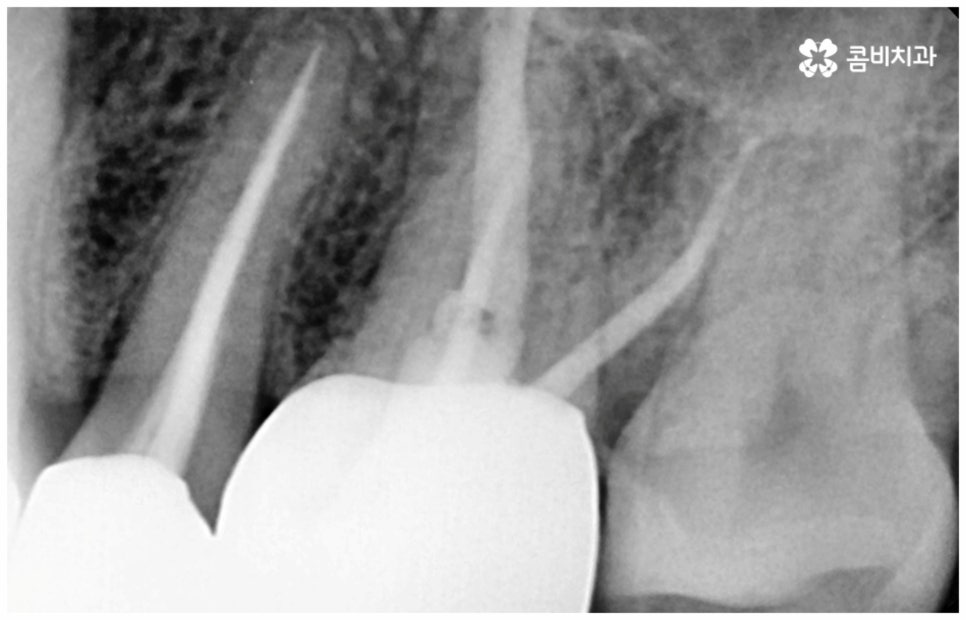

여기서 어금니신경치료 란 법랑질과 상아질을 지나 치아 안쪽 깊은 곳의 치수 조직까지 감염이 되었을 때 손상 부위를 모두 제거하고 치근관을 소독, 밀폐하는 치료를 의미하고 있는데요. 사람의 치신경은 아주 얇고 치근관의 모양과 개수는 모두 다 다른데 만약 끝이 구부러져 있거나 미세 부근관이 여러 갈래로 많이 퍼져 있는 경우, 신경관이 막힌 경우라면 신경을 제거할 때 난이도가 올라가므로 더욱 주의깊게 치료할 필요가 있어요.

감염 조직을 완전히 제거하지 않으면 통증이 지속될 수 있고 재발 가능성 또한 높아지므로 어금니신경치료 시 담당의 선생님의 높은 숙련도 및 세심한 기술력이 요구되고 있는데요. 혹시 모를 부작용을 방지하기 위해 3D CT 와 같은 정밀 진단 기계를 갖추고 신경관의 위치와 모양, 환자분들의 골조직 및 치아까지의 거리 등을 꼼꼼하게 파악하여 치료 계획을 세운 후 손상 부위를 세심하게 제거한다면 고난도의 경우라도 보다 안전하게 진행할 수 있어요.

또한 어금니 신경치료를 할 때 러버댐 장착은 필수적인데요 (사진에서 볼 수 있는 하얀막), 이와 같이 고무막으로 치료할 치아만 빼고 나머지는 격리시키는 이유는 해당 부위로 침이 유입되는 것을 막고 최대한 습기를 예방하여 (방습법) 치료의 효율성과 치과 재료 기능을 향상시키는 것, 환자와 시술자간 교차 감염을 막아 오염 확률을 낮추는 것, 신경 치료할 때 쓰이는 약제 또는 치아 삭제시 생기는 찌꺼기 등이 입 안으로 흘러 들어가는 현상을 방지하는 것 등등 환자분들을 보호하고 치료의 질을 높이기 위한 목적이니 안쪽 치아라서 조금 불편하시더라도 필요성에 대해서 잘 인지하시길 바라고 있어요.